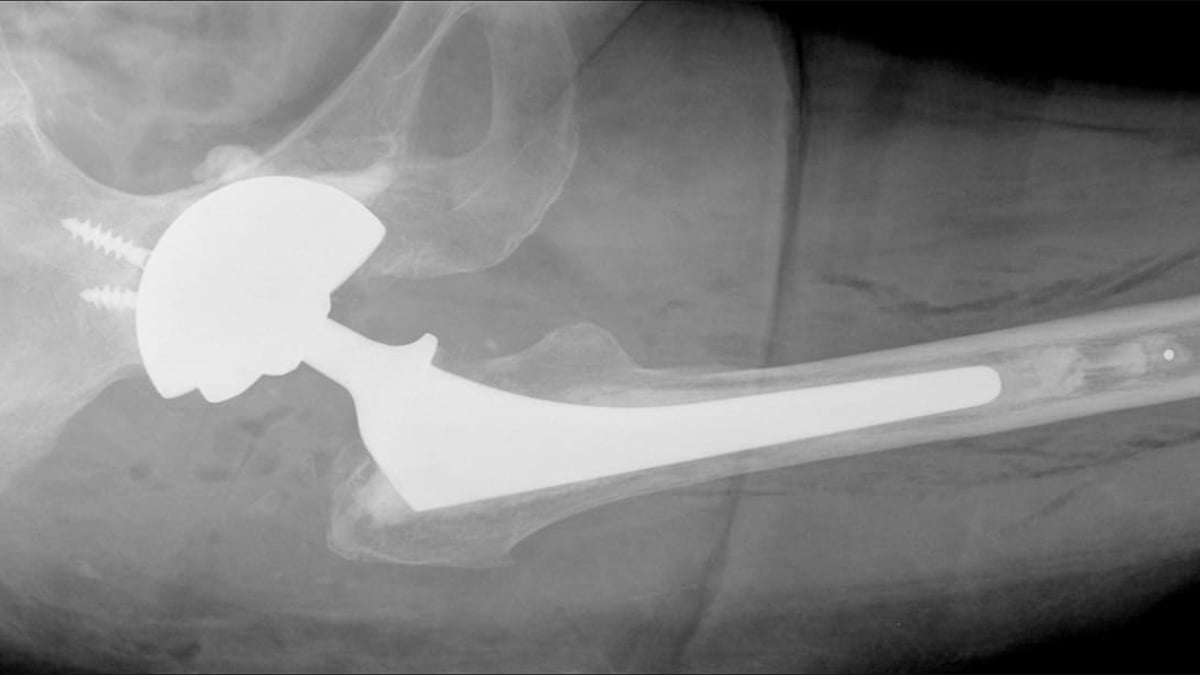

Vid omoperation av höftproteser kan risken för instabilitet minska med en metod där man cementerar fast dubbelskålar i en större metallskål, CMC-metoden.

– Vid omoperation av lösa höftproteser använder man sig ofta av stora skålar av metall. Detta kan leda till att höftprotesen hoppar ur led vilket är mycket smärtsamt och ofta kräver ytterligare operationer. En ny metod som utvecklats här på Akademiska sjukhuset innebär att man cementerar fast dubbelskålar i en större metallskål, vilket minskar denna risk, säger Anders Brüggemann, ST-läkare i ortopedi, Akademiska sjukhuset, som lett studien som publicerats i den vetenskapliga tidskriften Acta Orthopaedica.

Studien baseras på data från det loka höftprotesregistret i Uppsala och omfattade patienter som genomgick byte av höftledsprotes mellan 2008 och 2016. Totalt följde man upp 184 höftledsbyten på män och kvinnor i åldern 35-88 år (genomsnittsåldern var 67 år). Forskarna jämförde utfallet av två metoder, en där man cementerat fast dubbelskålar, så kallad DMCs, i en större metallskål, och en där man använde en enklare plastskål insatt i metallskålen.